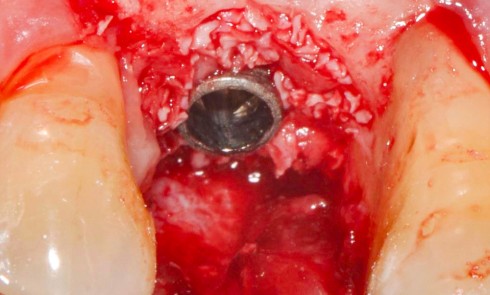

La patiente 65 ans ASA type I Pas de problèmes systémiques Pas de prise de médicaments Pas de consommation de...